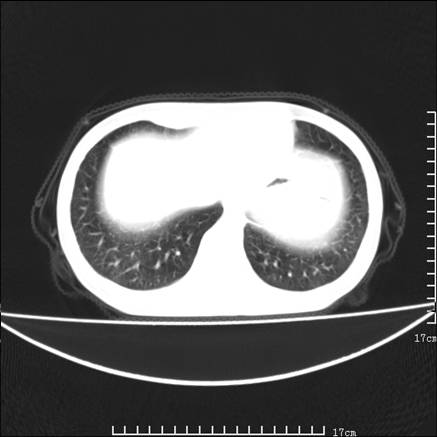

女,46岁,患胃溃疡多年,溃疡大小约1.0cm左右,后于5年前手术,病理为胃癌。主诉:半月前感冒后胸闷,气短,有咳嗽,无明显咳痰,无发热。偶有腰背部不适。

以下为高分辨扫描图像

双肺小叶间增厚,双肺散布粟米影和磨玻璃状影,以双肺上叶为重。结合病史考虑转移(癌性淋巴细管炎)可能性大。

结合病史:认为是典型肺部癌性淋巴管炎、淋巴结转移。请看图解。

支持 肺间质性肺炎,不除外癌性淋巴管炎,建议抗炎治疗复查---------小叶间隔增厚,磨玻璃影及片絮状影